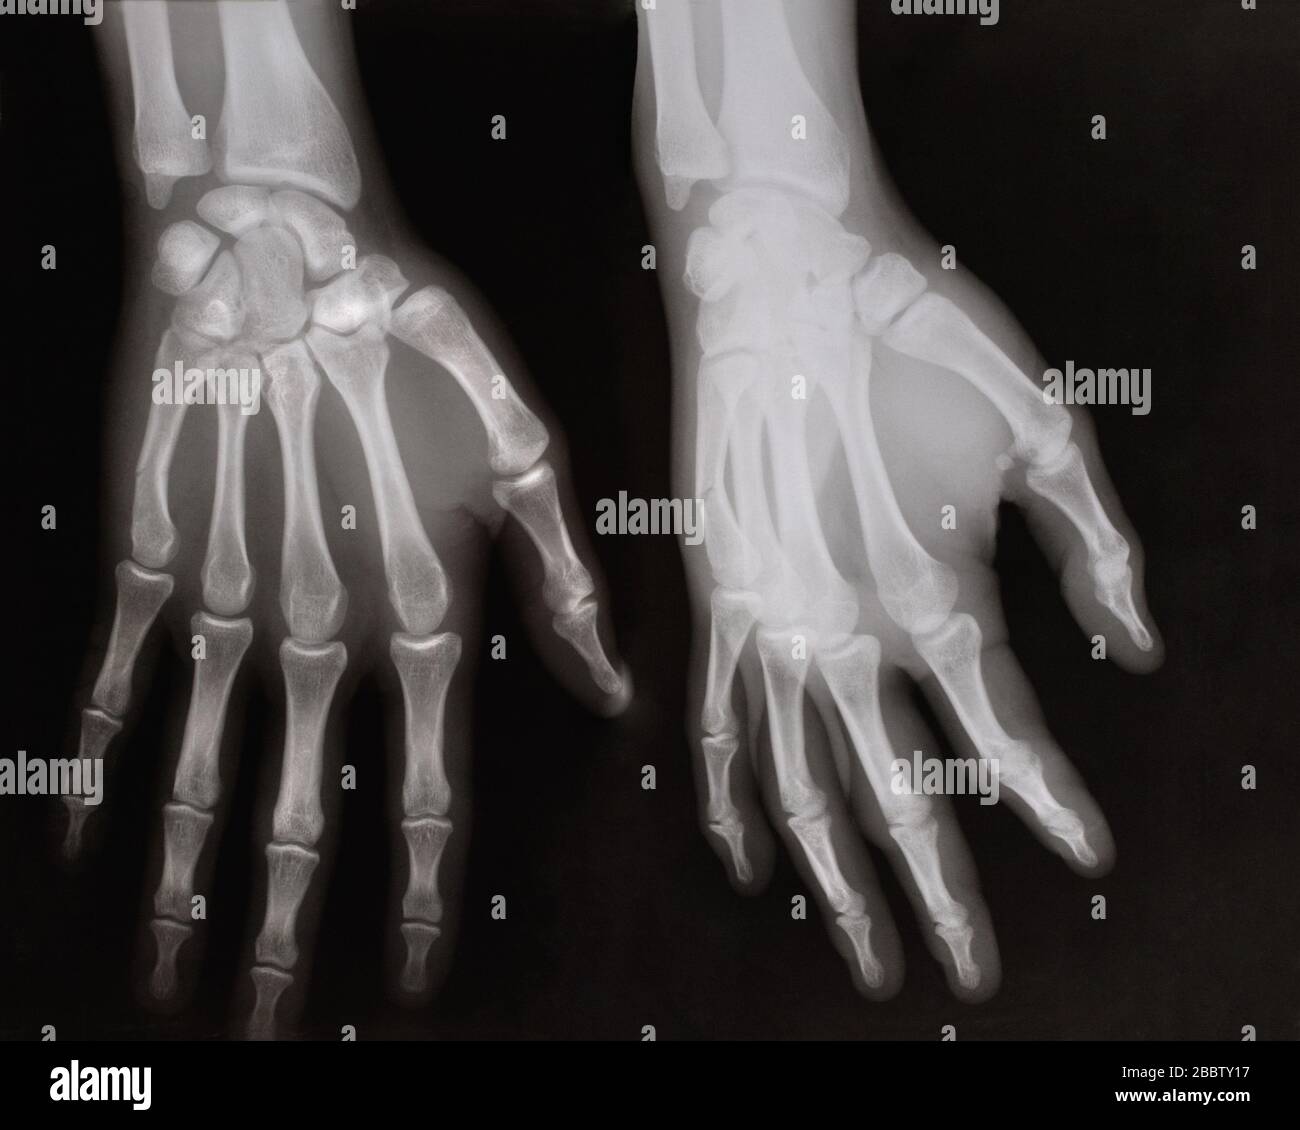

From www.alamy.com

Xray of human left hand Stock Photo Alamy Left Hand X Ray The hand comprises the metacarpal and phalangeal bones. The pa hand view is requested for diagnosing a variety of clinical indications such as rheumatoid arthritis, osteoarthritis, suspected fracture or dislocation and localizing. It uses a small amount of. Fractures and dislocations are usually straightforward to identify, so long as the potentially injured bone is fully visible in 2 planes. The. Left Hand X Ray.

Human Left hand on device x ray Medical Image Stock Photo Alamy Left Hand X Ray The hand comprises the metacarpal and phalangeal bones. Although additional radiographs can be taken. Fractures and dislocations are usually straightforward to identify, so long as the potentially injured bone is fully visible in 2 planes. The hand series consists of posteroanterior, oblique, and lateral projections. It uses a small amount of. The pa hand view is requested for diagnosing a. Left Hand X Ray.